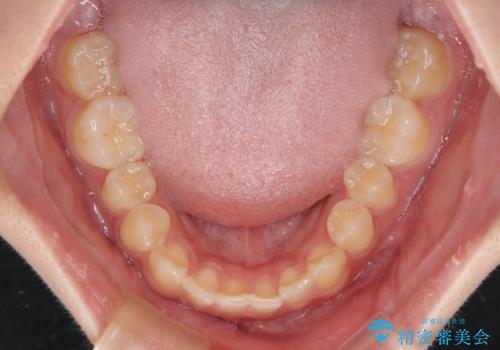

前歯のすきっ歯を治したい インビザラインによる矯正治療

- 上顎前歯の隙間を気にして来院された患者様です。

最終的には隙間は全て閉じ、綺麗な仕上がりとなりました。